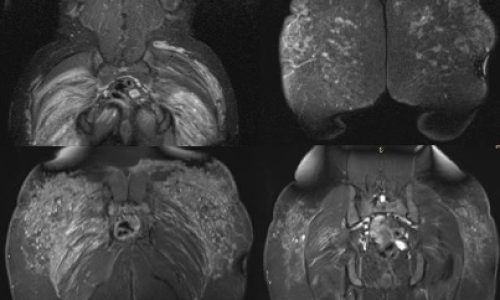

La importancia de la Resonancia Magnética en la extracción de biopolímeros